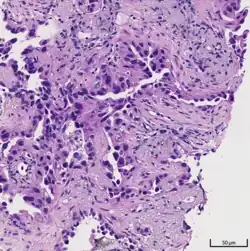

![]() | |

| A gross pathological specimen of a pulmonary adenocarcinoma, removed in a lobectomy. | |